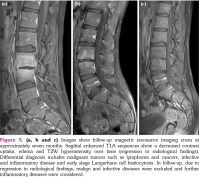

Lumbar vertebral computed tomography revealed a decrease in the right half of the disc height at the L3-4 intervertebral disc level (Figure 1a). Lumbosacral spinal magnetic resonance imaging (MRI) revealed in sagittal T2A sequences increased signal intensity, consistent with edema in the affected vertebrae and intervertebral disc (Figure 1b). The sagittal T1A sequences prior to contrast enhancement showed signal loss in the vertebral corpuses (Figure 1c), while sagittal postcontrast images showed a diffuse contrast uptake in the corresponding areas (Figure 1d). The axial postcontrast images showed involvement of the right paravertebral and foraminal soft tissues, and increased signal intensity consistent with the involvement of the right L3 nerve (Figure 2). Radiological findings were consistent with spondylodiscitis.

The patient was placed on steroid therapy, and a good response was achieved in terms of clinical and laboratory findings. Figures 1 and 5 present the MRI findings at baseline and during follow-up. Thus, early diagnosis provided good response to disease without organ damage.